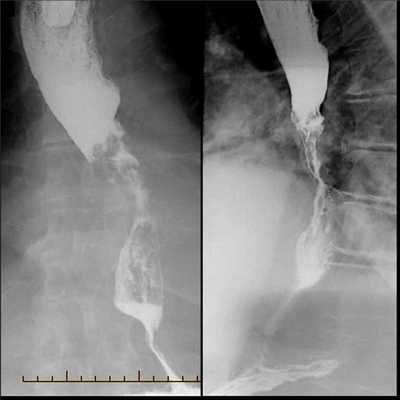

Диагностические мероприятия заключаются в первую очередь в рентгенологическом обследовании, при котором выявляют сужение просвета пищевода с неровными контурами и ригидными, инфильтрированными стенками. Выше сужения пищевод обычно несколько расширен. Иногда степень сужения столь велика, что даже жидкий барий очень тонкой струйкой с трудом проходит в желудок.

- Рентгенография с бариевым контрастом. Пациент принимает внутрь сульфат бария, который обволакивает стенки пищевода. Это позволяет увидеть на снимке рельеф стенок и обнаружить сужение просвета. На ранней стадии рак может иметь вид небольших круглых выпуклостей, то есть бляшек. На поздней стадии развития новообразование принимает вид большой опухоли неправильной формы, которая может вызывать сильное сужение пищевода. Рентгенография также позволяет диагностировать трахеопищеводную фистулу, то есть когда из-за разрушения новообразованием стенки пищевода на всю толщину пищевод начинает сообщаться с трахеей.

Рентгенодиагностика рака пищевода